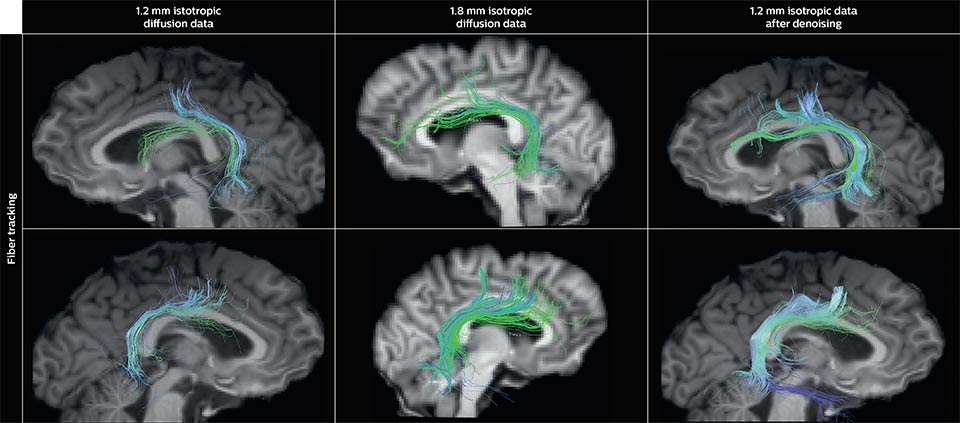

Denoising to improve quality

Using a non-local spatial and angular block matching technique to denoise raw diffusion weighted images. allows to push acquisition to lower spatial resolution and read human-connectome-project-like resolution from standard Philips Ingenia 3.0T MRI scanner. The data were acquired with spatial resolution of 1.2 x 1.2 x 1.2 mm in 13 minutes for 40 full brain DWI with b 1000 and one with b 0